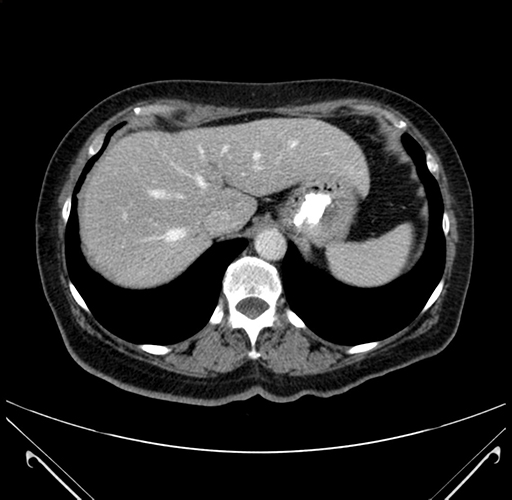

Pre-Chemo: Axial Venous